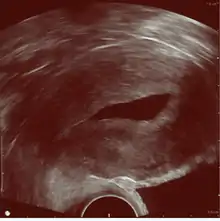

![]() Left hydrosalpinx on gynecologic ultrasonography | |